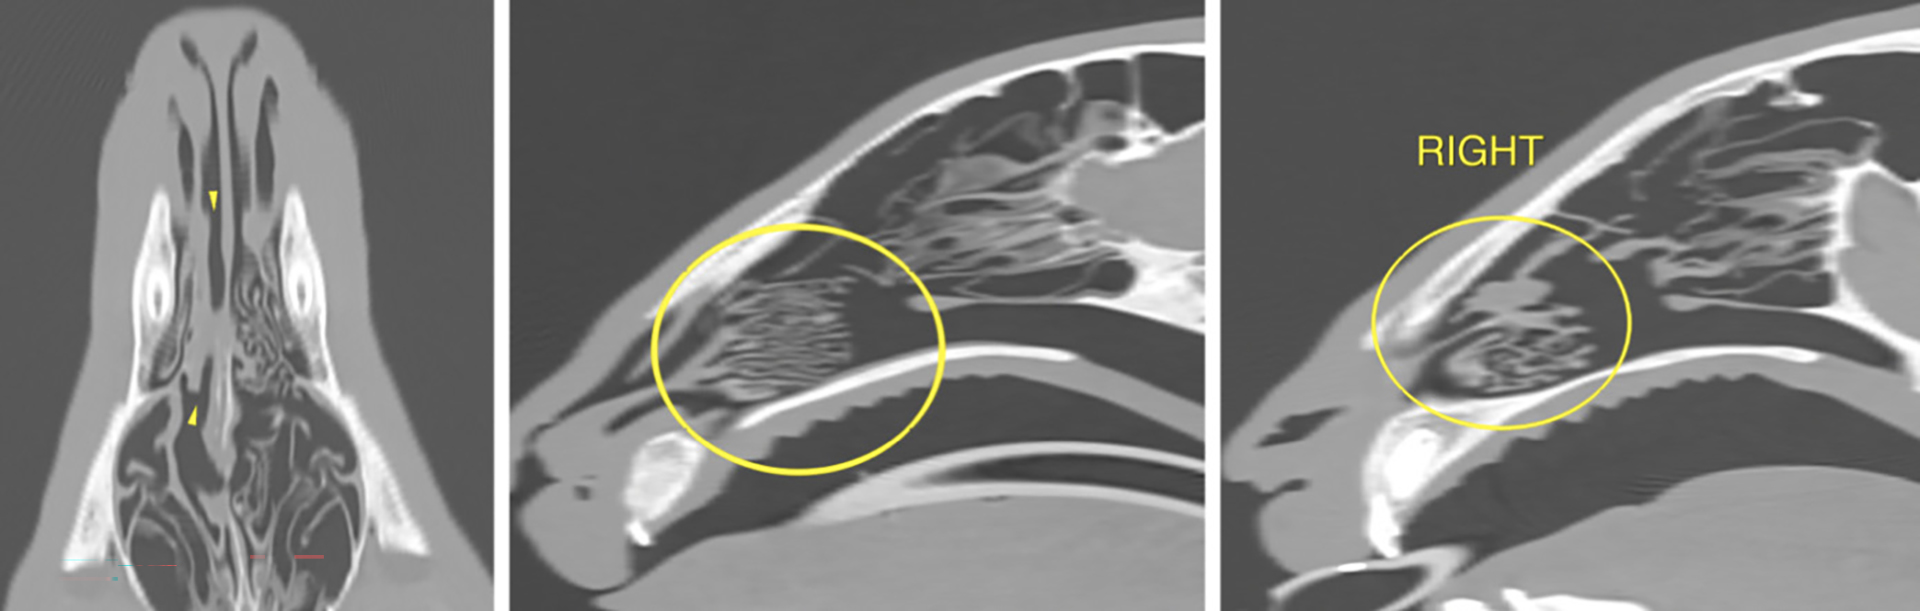

Figur 5. CT resultater. 1. Skjev neseskillevegg (gule piler). 2. Fokalt område med neseflod i venstre nesehule, som grenser til den midtre nesegangen (gul pil). 3. Normale frontalsinuser (gule piler). 4. Normale turbinater.

Foto: Magnus Harjen og VET.CT

CT-rapporten beskrev funn av destruktiv rhinitt i høyre halvdel av nesehulen, og ikke-destruktiv rhinitt i venstre halvdel av nesehulen (Figur 3-5). Frontalsinusene var tilsynelatende normale. Den kribriforme platen var intakt.